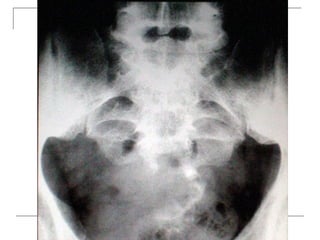

Plain radiograph

 AP

-loss of lumbar lordosis

-reduced disc space

-osteophytes

-deformity

-fracture (increase interpedicular distance)

-osteoporosis

-pedicle disruption